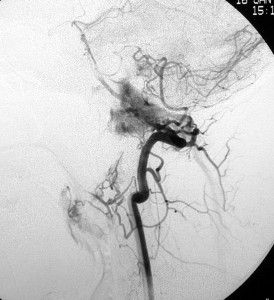

耳の聞こえと飲み込みが悪くなって発症(難聴と嚥下障害)した20代の患者さんのグロームス腫瘍 jugular paragangliomaです。左の頚動脈撮影 CAGでは,頸部の腫瘍におされて内頚動脈が前方に屈曲しています。外頚動脈から多くの血管が流入して血管腫のように濃い腫瘍陰影がみえます。右側の椎骨動脈撮影 VAGでは,頚静脈孔から頭蓋内の小脳延髄角部まで伸びた腫瘍が染まります。頭蓋内はPICAから頸静脈球と頸部には椎骨動脈の筋肉枝からの腫瘍血管がみられます。

頸部から頸静脈球を抜けてS上静脈洞内に入ります。これはクラスCかDか迷うところです。ちょっと難しい。またこのサイズでは,迷走神経と舌咽神経の機能を温存することができません。延髄方向へ伸展していますし年齢が若いので手術せざるを得ないものでした。

この腫瘍は放射線治療で制御できるものではないでしょう。手術で全摘出できて10年以上再発はありません。嚥下障害と強い嗄声が残りましたが,働いて社会生活はできています。